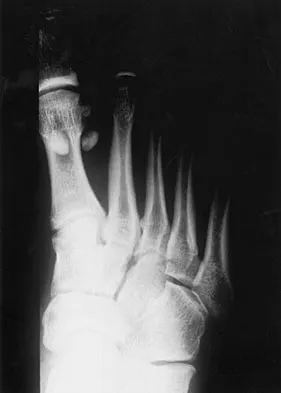

A 21-year-old football player who sustained a direct blow to the posterior hindfoot while making a cut is unable to bear weight on the injured foot. Examination reveals tenderness and swelling of the great toe metatarsophalangeal (MTP) joint. Radiographs are shown in Figures 9a and 9b. What is the most likely diagnosis?

Explanation

Turf toe occurs in collision and contact sports in which the athlete pushes off to accelerate or change direction and there is hyperextension of the great toe MTP joint. Typically, there is also axial loading of the posterior hindfoot, which increases the hyperextension of the MTP joint. The most common presentation is pain and swelling of the MTP joint and inability to hyperextend the joint without significant symptoms. With significant force, fractures of the sesmoids and plantar soft tissues can occur. The radiographs do not show a dislocation of the great toe MTP joint because it is concentrically located on both radiographs. However, the radiographs show a fracture of the lateral sesamoid or a diastasis of a bipartite lateral sesamoid. The medial sesamoid is also proximal indicating a rupture of the plantar (volar) plate. Therefore, the most likely diagnosis is a fracture of the lateral sesamoid with rupture of the plantar plate leading to proximal migration of the proximal fragment of the lateral sesamoid and the medial sesamoid. Rodeo SA, et al: Diastasis of bipartite sesamoids of the first metatarsophalangeal joint. Foot Ankle 1993;l4:425-434.